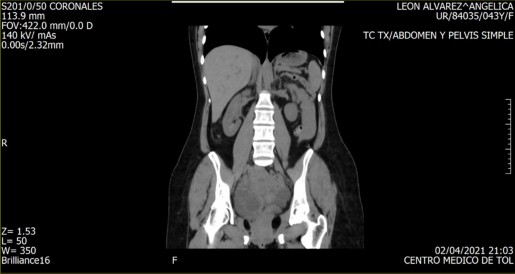

Imagen 1. TC TX. Abdomen y pelvis simple. Captura de video. (Autora, 2021).

Imagen 2. TC TX. Abdomen y pelvis simple. Captura de video. (Autora, 2021).

Imagen 3. TC TX. Abdomen y pelvis simple. Captura de video. (Autora, 2021)

Por supuesto, la producción artística no está exenta de un orden simbólico, mismo que determinará la relación de identificación imaginaria con la obra. Es a partir de esta lógica que se retomó una tomografía de tórax realizada ante un dolor inexplicable en el abdomen, inexplicable, porque le sucedieron diversos estudios que devolvían la interrogante sobre el origen del dolor en cuestión.

La tomografía señaló, entre otras cosas, la existencia de una “morfología ovoidea de bordes tenues y mal definidos, de densidad heterogénea, ya que presenta porciones sólidas y líquidas, mide en su conjunto 116x75mm en sus ejes mayores”. Cabe mencionar que, al revisar una y otra vez los videos que conforman el estudio, es imposible determinar dónde se encuentra la morfología ovoidea. Hay elementos que permiten una relación identificatoria, una pelvis, algún órgano, pero nada que pueda dar cuenta de la morfología en cuestión; fue necesario recurrir al orden simbólico de la medicina alópata para darle un nombre al elemento anómalo.

Adicionalmente, desde el ámbito imaginario se le nombró ‘Benedicto’, haciendo alusión a su carácter significante asociado a lo benigno, pero también al nombre del penúltimo papa, cuya imagen es asociada a un personaje nada benigno e incluso malvado. Bajo este nombre, fue posible establecer una identificación imaginaria con algo ominoso producido por el propio cuerpo y que, a partir de la tomografía, tenía una ambivalencia propia de Schrödinger: era al mismo tiempo benigno y maligno, y solo una intervención quirúrgica podría determinar su estado final.